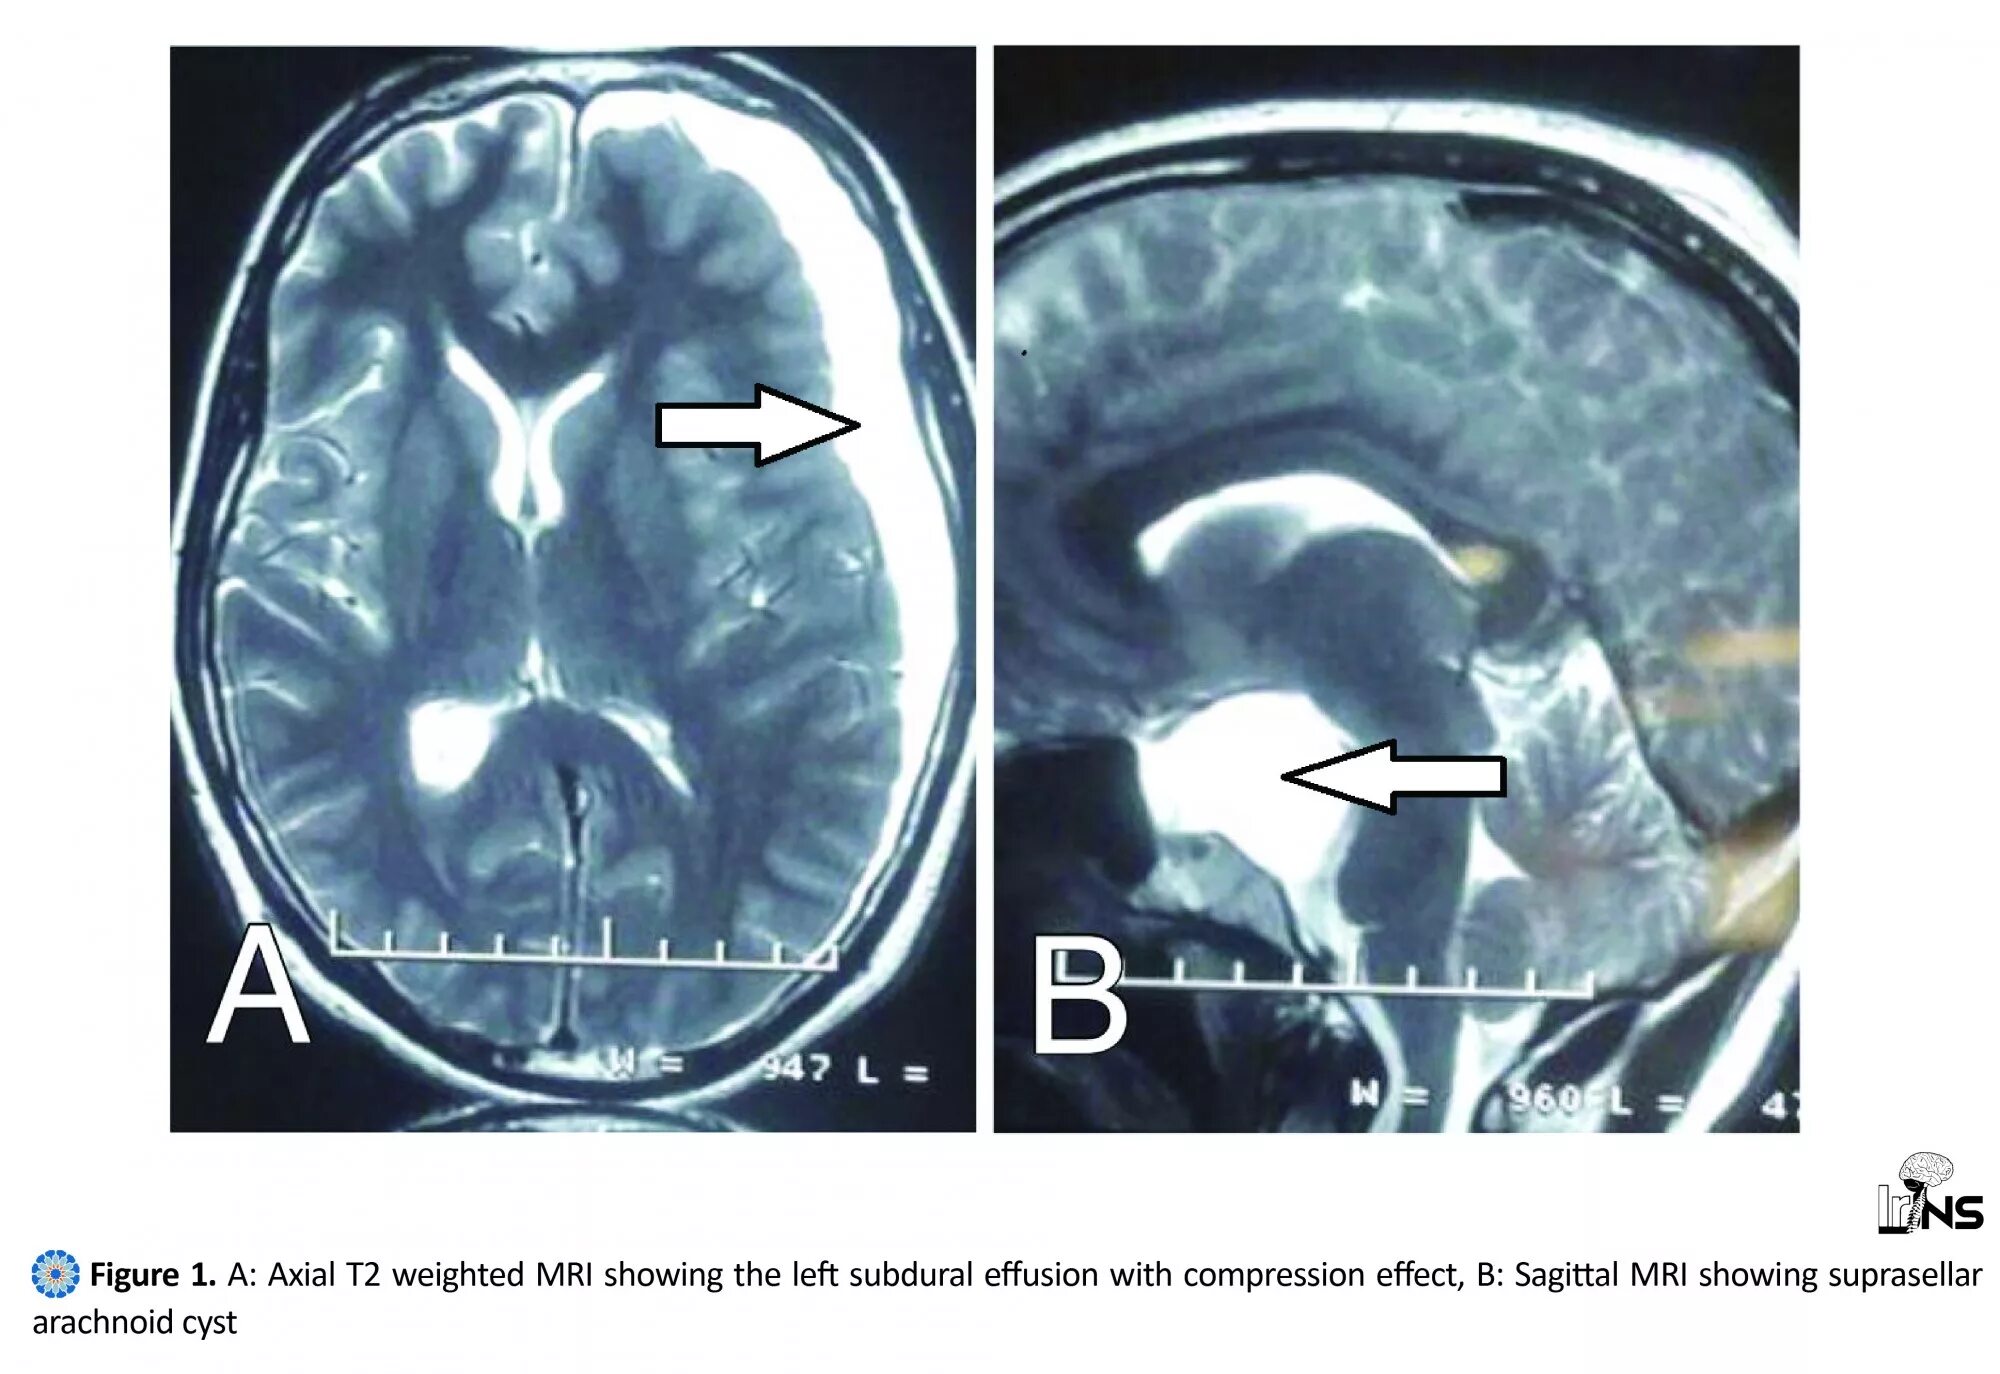

Ретроцеребеллярная ликворная киста